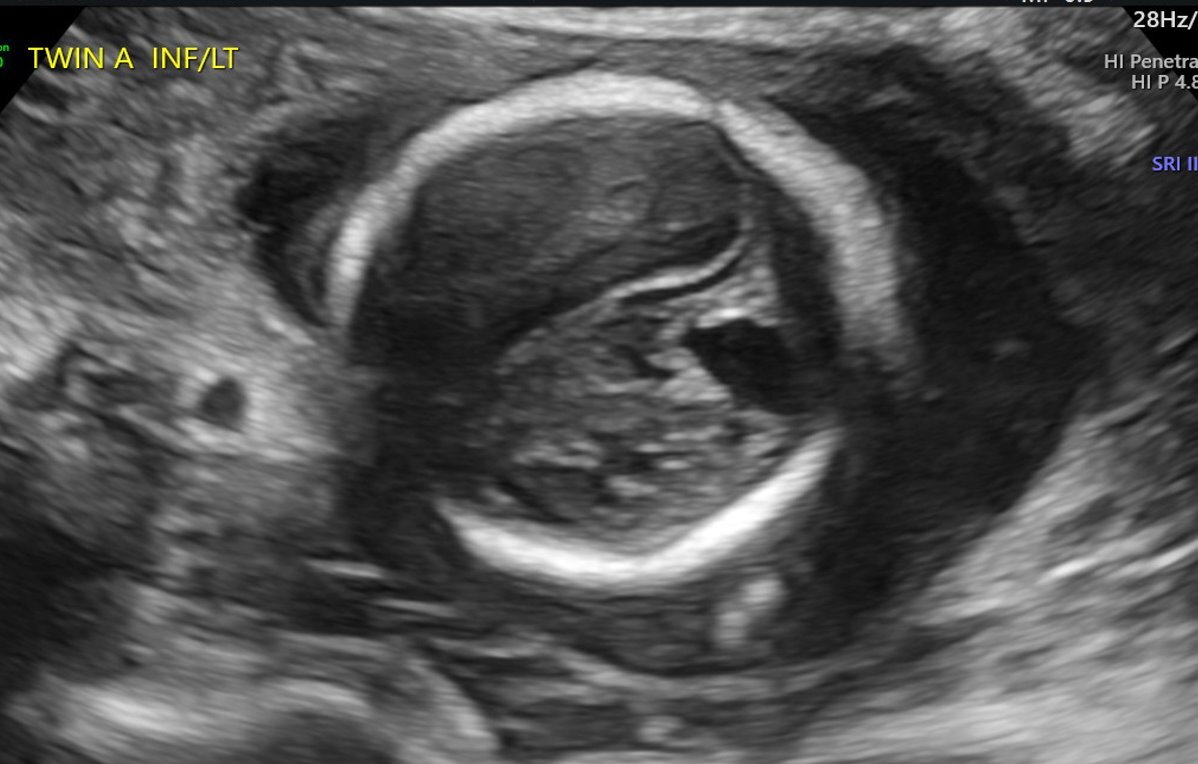

A 24-year-old gravida 1 with a dichorionic-diamniotic twin pregnancy at 16w1d gestation was evaluated by Maternal-Fetal Medicine who identified multiple possible cranio-facial abnormalities in Twin A on transabdominal ultrasound. This raised the concern for a possible chromosomal abnormality as well as holoprosencephaly as the cavum septum pellucidum was not visualized. A detailed transabdominal ultrasound performed at 16w1d provided the initial assessment of the abnormal-appearing left cerebrum of Twin A (Figure 1). The left cerebral ventricle was overall poorly visualized, however, the posterior aspect of the left ventricle appeared to be significantly more dilated compared to the normal-appearing right ventricle. The cavum septum pellucidum could not be visualized, the thalami appeared fused, and the temporal areas of the facies appeared more angulated than expected. The patient was scheduled for a fetal MRI which was performed at 19w1d gestation and showed complete architectural distortion involving the left cerebral hemisphere of Twin A, with a mass-like structure measuring approximately 2.4 x 2.3 x 1.8 cm, along with a loss of normal gray-white differentiation (Figure 2). The diagnoses based on this MRI were either a neoplastic growth or a migrational anomaly.